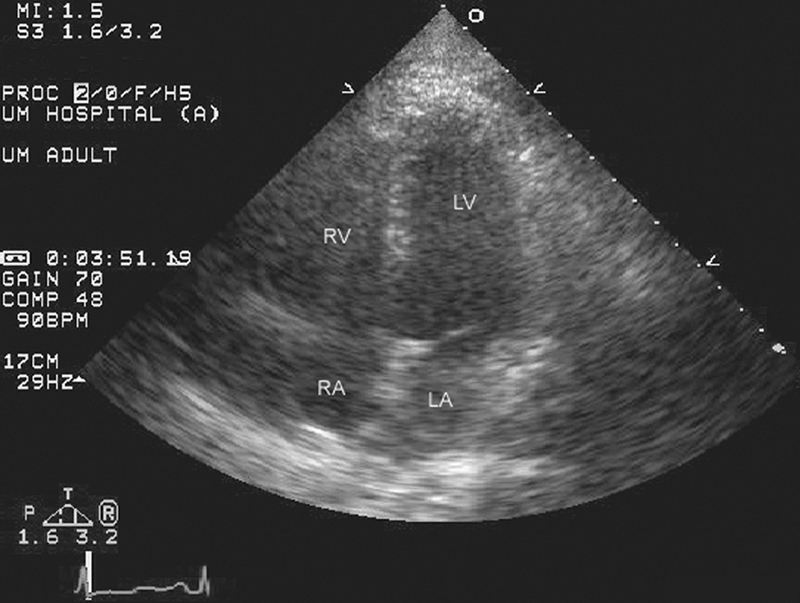

فحوصات تشخيصية لبعض امراض القلب والشرايين التاجية